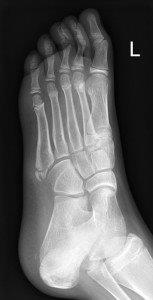

Avulsion fracture of base of fifth metatarsal

Avulsion fracture at base of fifth metatarsal

• Follow up Orthopaedic Fracture clinic 7- 10 days.

• If 4th and 5th inter-metatarsal joint involved (Jones Fracture), not suitable for CAM Boot.